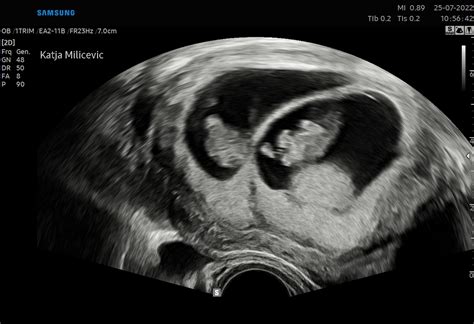

Med 11. in 14. tednom nosečnosti se običajno opravi ključna ultrazvočna preiskava, znana kot meritev nuhalne svetline (NS) v sklopu zgodnje morfologije ploda. Ta presejalni test predstavlja pomemben korak pri ocenjevanju tveganja za kromosomske nepravilnosti, predvsem Downov sindrom.

Meritev nuhalne svetline vključuje ocenjevanje debeline tekočine pod kožo na vratu ploda. Poleg tega se v sklopu te preiskave ocenijo še drugi anatomski označevalci, kot so:

- Prisotnost in oblika nosne kosti: Odsotnost ali hipoplazija nosne kosti je lahko povezana s povečanim tveganjem za kromosomske nepravilnosti.

- Pretok skozi venski duktus: Merjenje krvnega pretoka skozi specifično žilo v srcu ploda.

- Pretok skozi mitralno zaklopko: Ocena delovanja ene izmed srčnih zaklopk.

- Oblika obraza: Nepravilnosti v obliki obraza lahko nakazujejo na določene sindrome.

Združitev rezultatov meritve nuhalne svetline z drugimi anatomskimi označevalci ter rezultati dvojnega hormonskega testa (DHT), ki se običajno opravi v istem obdobju (10.-14. teden) in vključuje merjenje ravni dveh nosečniških hormonov v krvi nosečnice (β-hCG in PAPP-A), omogoča izračun tveganja za kromosomske nepravilnosti. Zanesljivost kombiniranega testa (UZ + DHT) doseže okoli 90 %.